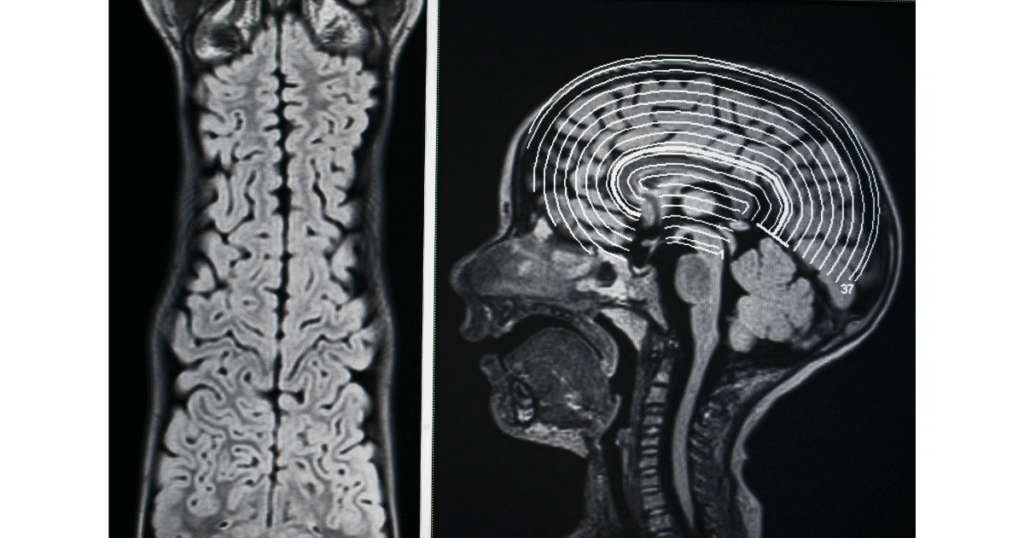

- Eletroencefalograma (EEG): É o exame que capta a atividade bioelétrica dos neurônios corticais através de eletrodos. Na prática clínica, ele é essencial para identificar focos epileptogênicos, crises não convulsivas e para o protocolo de determinação de morte encefálica, onde buscamos a ausência total de ondas elétricas (silêncio elétrico).

- Ressonância Magnética (RM): Oferece uma visão detalhada da anatomia tecidual em alta resolução. Diferente da tomografia, a RM permite visualizar com precisão áreas de desmielinização, isquemias precoces e pequenas lesões estruturais no parênquima cerebral que poderiam passar despercebidas, sendo fundamental para diferenciar diagnósticos diferenciais complexos.